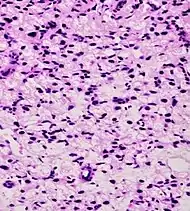

Intraductal carcinoma of the prostate with an infiltrative growth pattern may be morphologically difficult to distinguish from invasive cancer. One focus shows comedonecrosis (arrow), morphologically suggesting Gleason pattern 5 invasive carcinoma (a haematoxylin and eosin, b CK5/6)[19]

Intraductal carcinoma of the prostate with very patchy basal cells identified by immunohistochemistry. At least some of the glands lacking basal cell immunoreactivity represent intraductal rather than invasive carcinoma (a haematoxylin and eosin, b CK 5/6)[19]